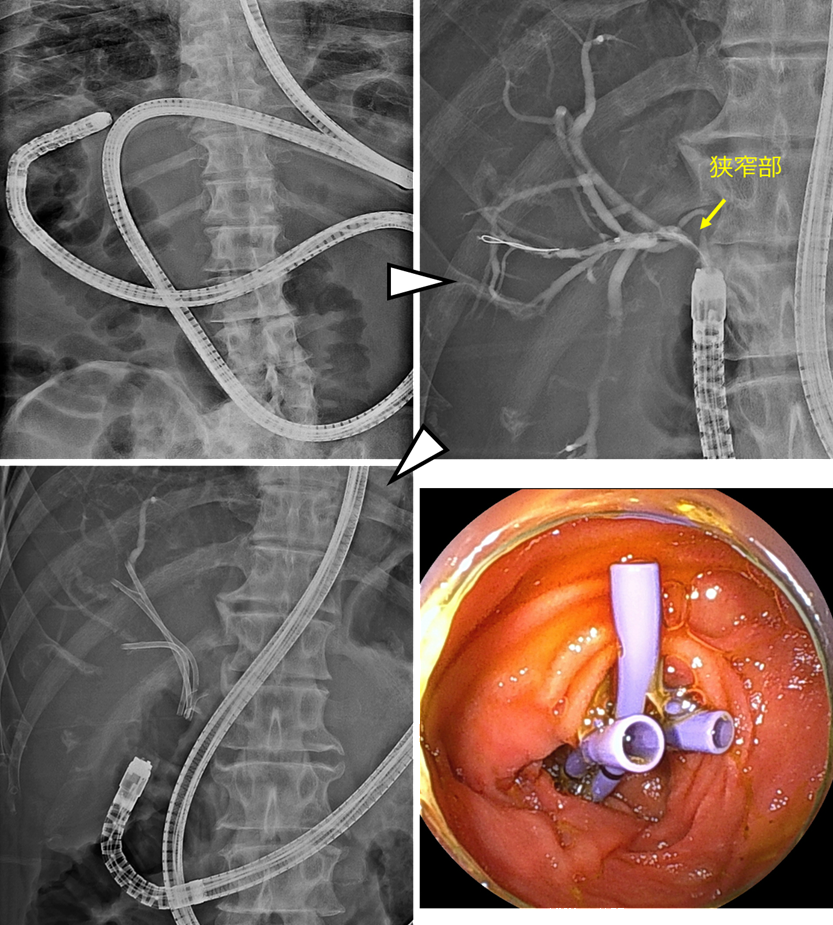

膵癌による胆道狭窄に対して胆道ドレナージを行った症例

膵癌に対して化学療法中でした。腫瘍によって、胆汁の流れ道である胆道が狭窄し、黄疸を発症し化学療法の中止を余儀なくされました。そのため、ERCPでの胆道ドレナージを行う方針としました。

まず内視鏡を十二指腸まで進め、胆管と膵管が合流する十二指腸乳頭(主乳頭)を確認します。専用のカテーテルを用いて胆管を選択し、ガイドワイヤーを胆管内へ挿入します。必要に応じて内視鏡的乳頭切開術を行い、胆管への処置を行いやすくします。これらの操作は透視装置(X線)で位置を確認しながら安全に進めます。

透視画像で胆道の狭窄を確認します。狭窄部は胆管の下流側にあり、この部位は遠位胆管と呼ばれます。この遠位胆管の狭窄部にステントを留置することで、胆汁の流れを改善します。本症例では金属ステントを1本留置し、胆汁の流れを確保しました。

本症例では高度の黄疸を認めていましたが、速やかに胆道ドレナージを行うことで黄疸は改善し、その後化学療法を再開することができました。

肝門部領域胆管癌による胆道狭窄に対して胆道ドレナージを行った症例

肝門部領域胆管癌によって閉塞性黄疸を発症し、複数のステントを留置した症例を示します。

本症例では化学療法中に黄疸が出現しました。MRCP検査では、胆管の左枝、前区域枝、後区域枝のそれぞれに狭窄を認めました。

ERCPを行ったところ、同様にこれらの胆管に狭窄を認めたため、それぞれの胆管に対して胆汁の流れを確保する必要がありました。そのため、3本のプラスチックステントを留置しました。

ステント留置後、黄疸は速やかに改善し、その後化学療法を再開することができました。

また、複数本のステントが必要な状況であっても、症例ごとの病状や胆管の走行、狭窄の形態などを考慮し、金属ステントを留置することもあります。当科では、一人ひとりの状態に合わせて、最適な胆道ドレナージを行うよう心がけています。

左上:Roux-en-Y再建後でした。ダブルバルーン内視鏡を用いました。

右上:到達後、胆管造影を行い、狭窄部の確認をしました。

左下・右下:前区域枝に2本・後区域枝に1本のステントを留置しました。